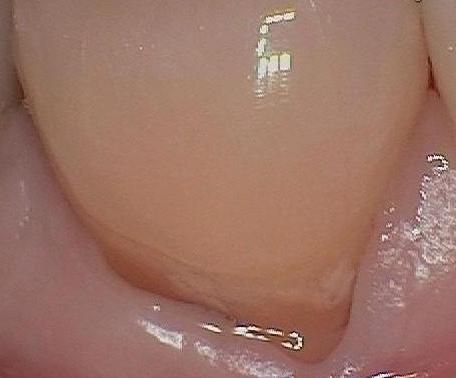

Below is a Dental Health Partners patient who has very good oral hygiene but is also a scrubber when brushing: